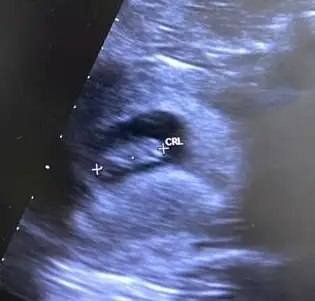

Kızlar selam 9+2 deyiz ultrason 8+5 e ait cinsiyet tahmini yapacak var mı ? :) <3

WhatsApp Image 2023-06-15 at 11.48.39.webp